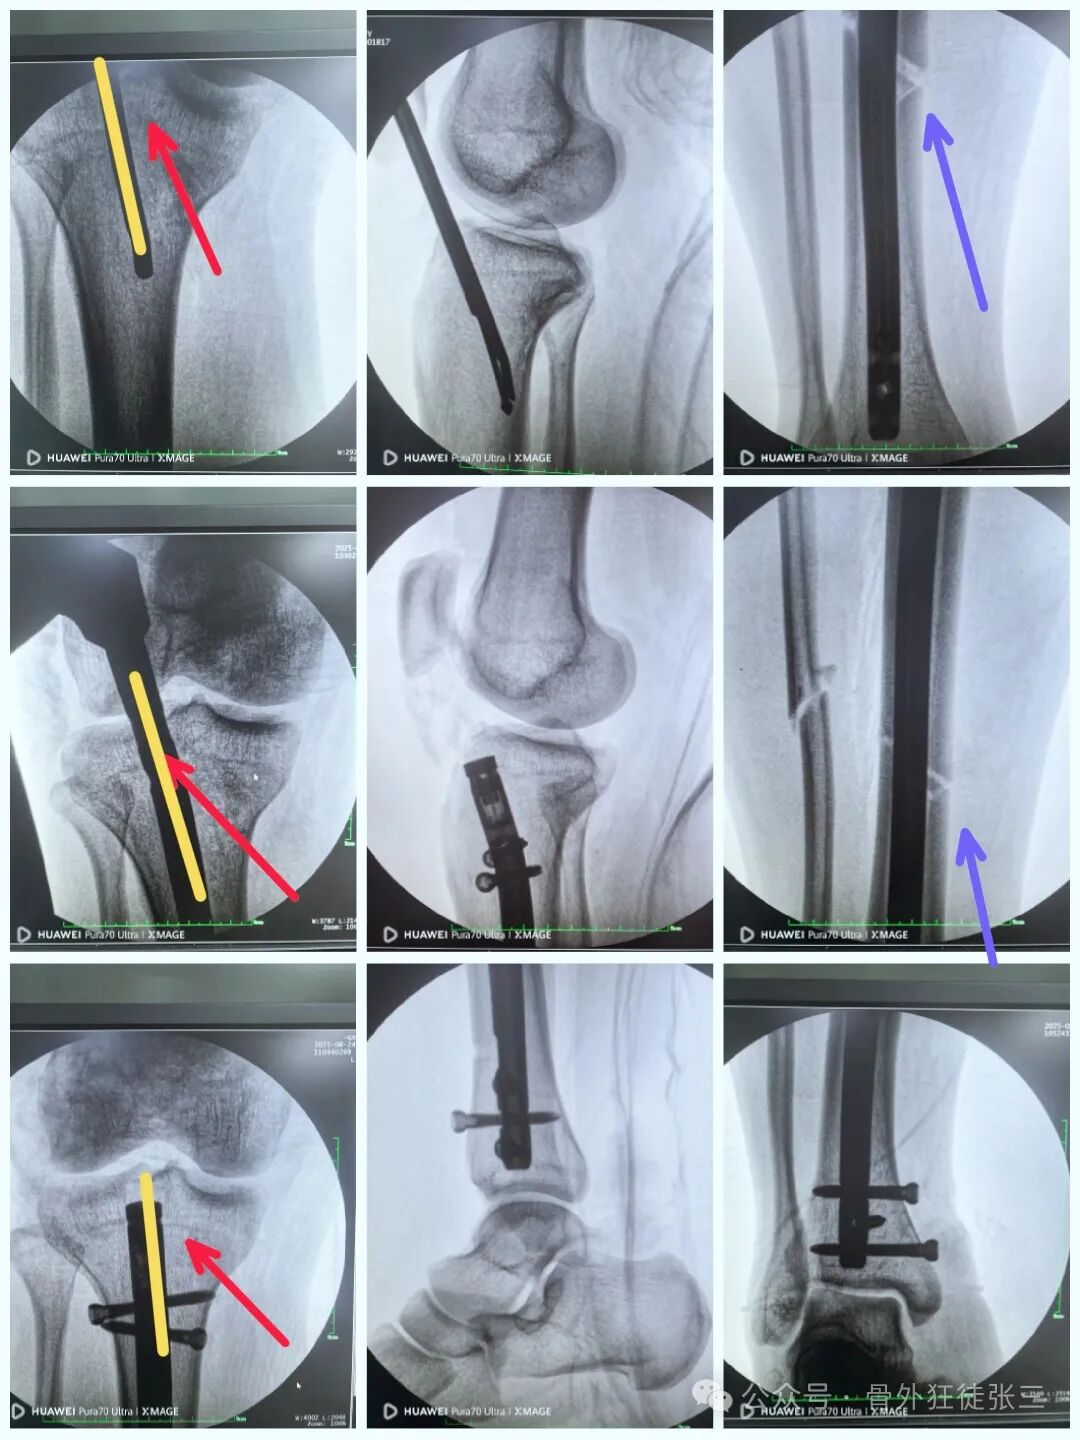

近年来,髌旁外侧入路髓内钉技术因复位精准、创伤小、康复快等特点,得到了广泛的应用。本文将围绕一例胫腓骨骨折案例,详细介绍该手术过程,为临床同仁提供思路与参考。

远端安装瞄准架

骨折间隙顺利缩小

锁近端两枚锁钉

所以直接就没有打静态孔

尾帽顺利锁定

侧位复位良好

踝关节侧位钉子长度满意,居中

如何避免进针点偏外的处理

就能顺利纠正

6,扩髓时,不需要复位,但是需要扩到过狭窄部位,不要一杆子扩到底,容易不居中。

7,髓内钉本身就是复位工具,在此时依靠髓内钉+手法,几乎都能顺利复位。

8,锁钉基本现在的瞄准器都很准,基本没有难度。